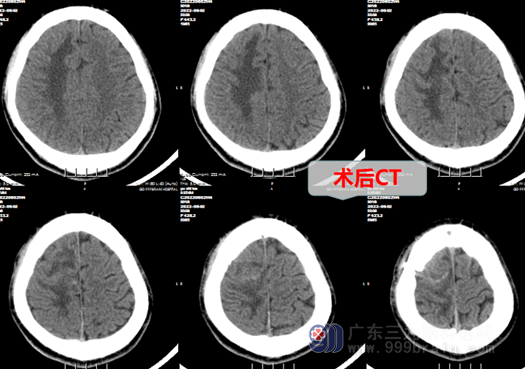

经我院欧阳辉教授经验丰富,带领神经外十科专业团队精准诊疗,对此患者分析、讨论后,很快得出明确诊断,再经得家属同意后,决定给患者在全麻下行右侧额叶中央前回脑脓肿清除术+脓肿壁切除术。手术比较微创,导航定位右侧额叶中央前回病灶后,在其稍前方,先穿刺抽脓,再切开约2cm长的脑沟,保护好周围脑组织,尤其是运动区,剖开脓腔,清除腔内脓液及精确分离切除脓肿壁,手术非常顺利。

术后,患者神志清醒,头部切口逐渐愈合,患者的左侧肢体功能也一步一步恢复正常:从不能动弹到可以自由下床活动,左侧手脚都能自由活动了。徐某及家属都非常高兴,医生给他揪出了急性偏瘫的元凶-功能区脑脓肿,又使年轻的他对前途充满了希望。2022年5月12日出院当天,徐先生高高兴兴地给医院外十科医护人员写下了充满真情的感谢信。